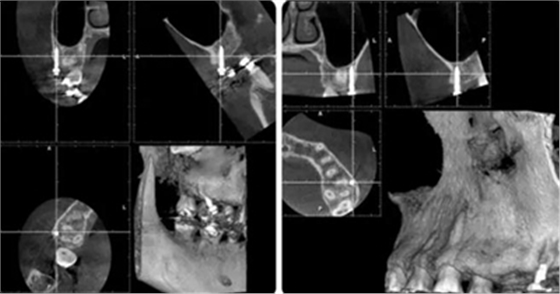

治療8個(gè)月,換0.018*0.025"CuNiTi弓絲,植入支抗釘,植入位點(diǎn)為上頜第一磨牙根上方顴牙槽嵴處,使其與牙根平行。同時(shí)嘗試性牽引遠(yuǎn)移上牙列。

(3)全牙列遠(yuǎn)移種植釘植入位點(diǎn)為上頜第一磨牙根上方顴牙槽嵴處,使其與牙根平行,在術(shù)前需CBCT確認(rèn)骨量,否則有脫落或無(wú)法植入的可能。